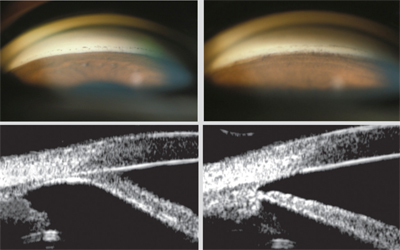

전방각 검사를 시행하는 전방각 검사용 특수렌즈인

전방각경 (gonioscopy lens) 중에서 각막의 직경보다 더 작은 전방각경으로

각막의 중심부를 누르는 방법을 사용합니다.

이는 전방각경검사를 통해 주변부 전방각을 관찰도 하면서,

폐쇄된 전방각을 열기도 할수 있는 처치 두가지가 동시에 가능합니다.